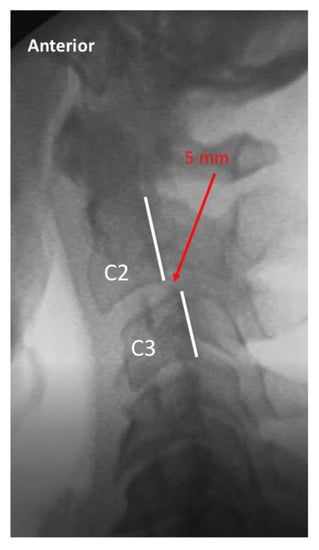

| Translation (lat) | C2-7 | Lateral flexion-extension | Maximum anterior (in flexion) or posterior (in extension) translation of vertebral body relative to adjacent inferior vertebra, measured at posterior vertebral body line | 2 mm or less anterior or posterior translation |

| C2-7 translation (lat view) | 0–2 mm | 0–2 mm > 2 mm |

| > 2–3 mm | ||

| > 3–4 mm | ||

| > 4 mm | ||